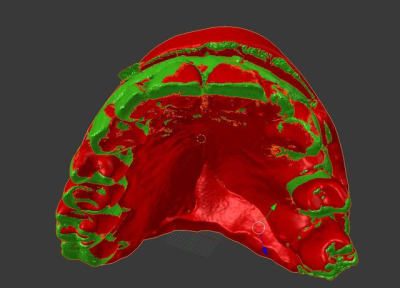

1) plâtre cône beam dans invesalius

2) cone beam vs cam3d

3) collage dans blender

4) résultat

toujours avec mon nouveau jouet, je n'avais jamais testé mais cela fonctionne parfaitement bien

plus besoin de faire couler le plâtre par le labo!!!

un scan ou un cone beam de l'empreinte suffit